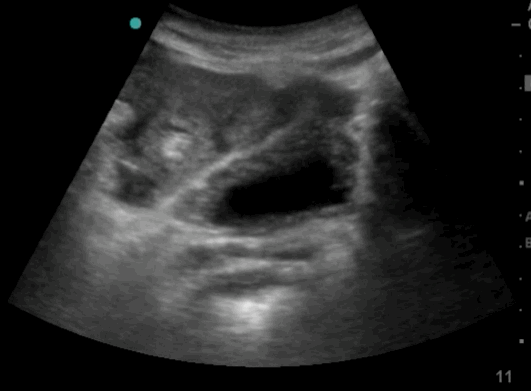

22_Abdomen_LUQ_Perisplenic

Free fluid between diaphragm and spleen. Further fluid is seen in the pleura.